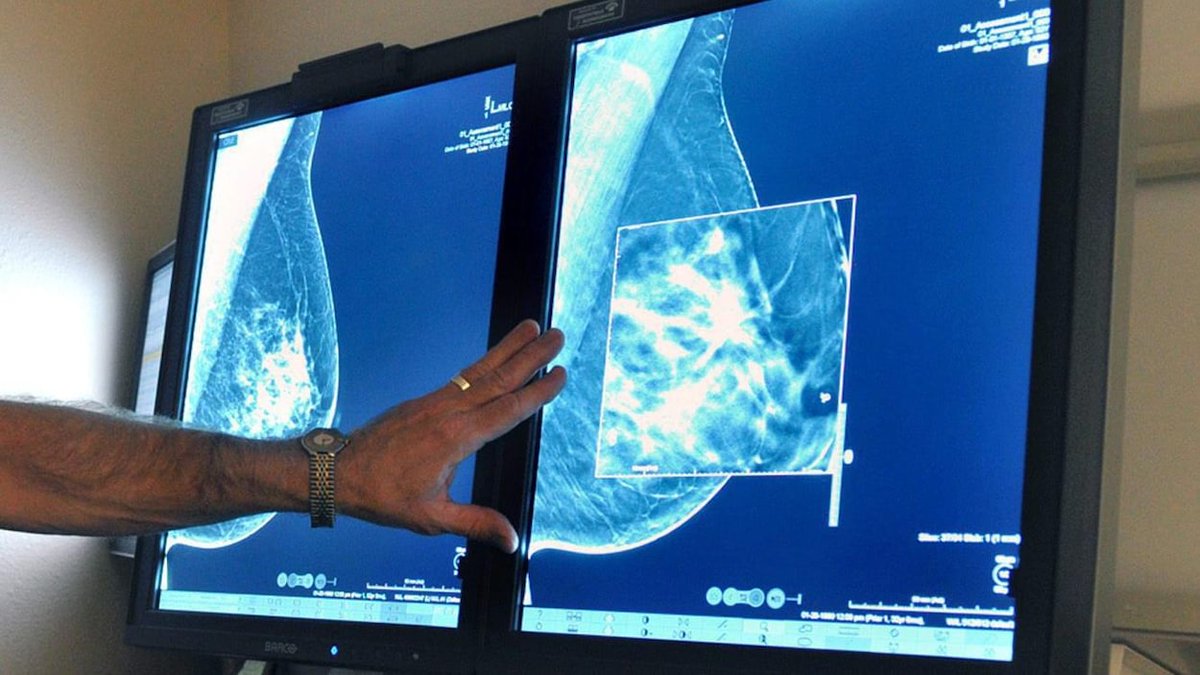

Report warns persistent access issues are putting cancer patients at risk